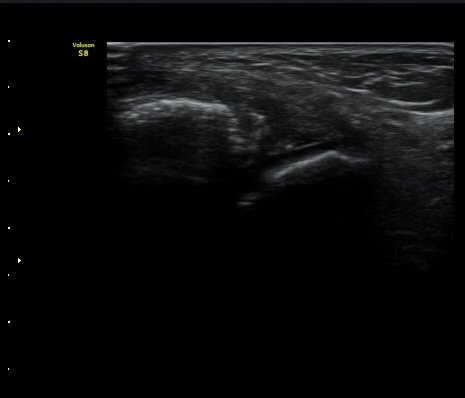

3ÁÖ ÈÄ ÃßÀû°Ë»ç»ó °üÀý³» ºÎÁ¾ÀÌ ¼Ò½ÇµÇ°í(±×¸² 4). Àü°Å°ñºñ°ñÀδëÀÇ Àú¿¡ÄÚ ºÎÁ¾ÀÌ

°¨¼ÒÇÏ°í °ß¿­°ñÀý °ñÆíÀº ºñ°ñ °¡±îÀÌ À§Ä¡Çϰí ÀÖ´Ù(±×¸² 5, 6).

ÃÊÀ½ÆÄ Åõ½ÃÇÏ ºÎÇϰ˻翡¼­ ºñ°ñ°ú ÀδëºÎÂøºÎ¿Í  ºñ°ñ°ú °Å°ñ»çÀ̰¡ ¹ú¾îÁöÁö ¾Ê´Â´Ù

(樨毢 2).

±×¸²6) 3ÁÖ ÈÄ ÃßÀû°Ë»ç